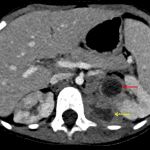

- Mild cortical thinning in the upper pole of the right kidney with adjacent calyceal enlargement

- Mild right hydroureteronephrosis with urothelial thickening

- Mild circumferential mural thickening of the urinary bladder with layering echogenic material

Mild fulness of the left renal pelvis and mild right hydroureteronephrosis with bilateral urothelial thickening in addition to bladder wall thickening, likely relating to urinary tract infection. No obstructing ureteral calculus identified.

Likely mild cortical scarring at the upper pole of the right kidney with adjacent calyceal enlargement, which may represent sequela of prior infection.